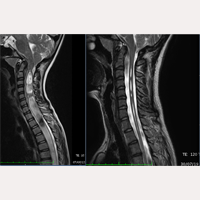

Hola, sóc mare d’una filla que es va operar amb 8 anys d’edat mitjançant la secció del filum terminale al desembre de 2013 i va ser la quarta pacient japonesa operada per l’Institut Chiari de Barcelona. La nostra filla pateix Malformació d’Arnorld Chiari I, Siringomièlia i Escoliosi idiopátiques. Han passat 6 anys i mig des que es va operar i tot ha anat molt bé. La nostra filla tenia la cavitat siringomiélica molt greu, fins a la zona lumbar, però al cap de 6 mesos de la intervenció, va disminuir fins a la meitat i al cap de 18 mesos, fins a un terç. La cavitat encara persisteix, però va disminuint a poc a poc. Després de 2 anys i mig, es va observar algun canvi en el descens de les amígdales cerebel·loses, i després de 4 anys i mig va haver-hi encara més millores. El metge de la nostra filla al Japó se sorprèn pel resultat de la secció del filum terminale, i ens diu que, com ha disminuït tant la cavitat fins ara, no tindria problema si no presenta símptomes. No obstant això, com no es pot evitar completament la progressió de l’escoliosi, l’Institut ens va recomanar el mètode Schroth i al cap de 4 mesos de l’operació, la nostra filla va començar a practicar-ho. Durant 4 anys, vam poder frenar la seva progressió, però quan la nostra filla va entrar en el període de desenvolupament, al desembre de 2018, va empitjorar fins a 48 graus de la curvatura, per la qual cosa decidim canviar el centre de la rehabilitació, i al cap d’1 mes va millorar fins a 33 graus i seguim les indicacions per millorar l’escoliosi.

La nostra filla va ser diagnosticada d’Escoliosi quan tenia 5 anys i durant 3 anys li van fer controls. Amb 7 anys, li van recomanar fer ressonàncies magnètiques perquè la seva curvatura va empitjorar. Va ser llavors quan descobrim que, a més d’Escoliosi, tenia la Malformació de Chiari I i Siringomièlia. Simultàniament ens van dir que la seva Escoliosi era deguda a aquestes dues malalties i que primer havia de tractar-les mitjançant neurocirugía per poder començar el tractament d’Escoliosi.

A la visita amb un neurocirurgià, ens van dir que el tractament seria la Craniotomía i com la cavitat siringomiélica arribava fins la zona lumbar, s’havia d’operar de seguida ja que era greu. “Per què ha de passar tot això a la nostra filla?, si tan sols té 8 anys!!” Va ser el meu sincer sentiment en aquell moment. El meu marit i jo, sense estar-ne segurs, comencem a buscar per internet informació sobre les malalties i el seu tractament. Ens assabentem que la Craniotomía podria ocasionar dues o tres reintervencions a mesura que anessin empitjorant els símptomes, i malgrat ser una intervenció invasiva amb alt risc, pot ser que no millorin els símptomes. Trobem testimis de pacients operats mitjançant Cranioctomía en els que comenten que l’operació deixa seqüeles greus i llavors comencem recerques sobre les alternatives a la Craniotomía.